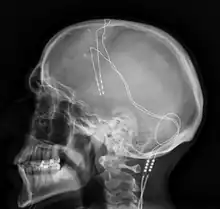

Components and placement

The DBS system consists of three components: the implanted pulse generator (IPG), the lead, and an extension. The IPG is a battery-powered neurostimulator encased in a titanium housing, which sends electrical pulses to the brain that interfere with neural activity at the target site. The lead is a coiled wire insulated in polyurethane with four platinum-iridium electrodes and is placed in one or two different nuclei of the brain. The lead is connected to the IPG by an extension, an insulated wire that runs below the skin, from the head, down the side of the neck, behind the ear, to the IPG, which is placed subcutaneously below the clavicle, or in some cases, the abdomen.[8] The IPG can be calibrated by a neurologist, nurse, or trained technician to optimize symptom suppression and control side effects.[35]

DBS leads are placed in the brain according to the type of symptoms to be addressed. For non-Parkinsonian essential tremor, the lead is placed in either the ventrointermediate nucleus of the thalamus or the zona incerta;[36] for dystonia and symptoms associated with PD (rigidity, bradykinesia/akinesia, and tremor), the lead may be placed in either the globus pallidus internus or the subthalamic nucleus; for OCD and depression to the nucleus accumbens; for incessant pain to the posterior thalamic region or periaqueductal gray; and for epilepsy treatment to the anterior thalamic nucleus.

All three components are surgically implanted inside the body. Lead implantation may take place under local anesthesia or under general anesthesia ("asleep DBS"), such as for dystonia. A hole about 14 mm in diameter is drilled in the skull and the probe electrode is inserted stereotactically, using either frame-based or frameless stereotaxis.[37] During the awake procedure with local anesthesia, feedback from the person is used to determine the optimal placement of the permanent electrode. During the asleep procedure, intraoperative MRI guidance is used for direct visualization of brain tissue and device.[38] The installation of the IPG and extension leads occurs under general anesthesia.[39] The right side of the brain is stimulated to address symptoms on the left side of the body and vice versa.